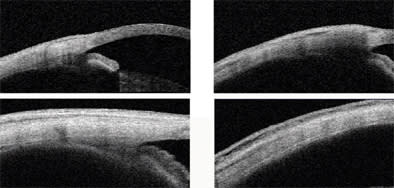

The angle of the incision through the sclera may be directed in an oblique, tunneled fashion (Figures 2 and 3), as rectangular radial incisions may remain open, inducing vitreous or drug reflux under the conjunctiva, as well as severe chemosis and even hypotony in vitrectomized eyes.14,15 Dr. Meyer observes persistent unsealed sclerotomies following radial injections using a 30-gauge needle, requiring secondary suturing to seal the penetrating scleral wound.16 The depth of the insertion may vary between 5 to 7 mm according to Anne Fung, MD, so that the tip of the needle is placed in the mid-vitreous. The drug is then gently injected into the vitreous cavity.

Figure 2. Schematic drawing of the injection procedure: The conjunctiva is moved upwards so that the conjunctival hole and the site of the scleral penetration are not on top of each other. After an initial lamellar penetration of the outer sclera, the needle is moved upwards for a full-thickness penetration.

Figure 3. Examination of the injections site 15 minutes after the injection with the anterior-segment OCT scan (Visante): The radial injection remains open and visible, whereas the tangential oblique injection is not detected on OCT.